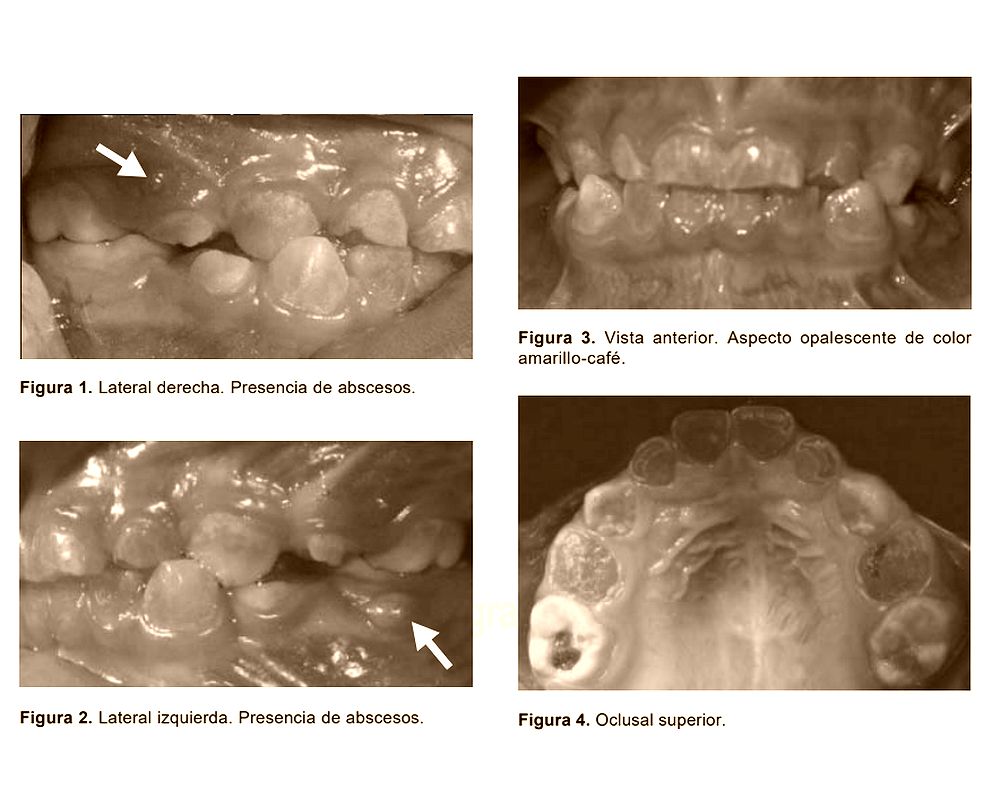

From www.odontovida.com

¿Qué es la Dentinogénesis imperfecta? Reporte de un caso OdontoVida What Is Dentinogenesis The hereditary dentine disorders, dentinogenesis imperfecta (dgi) and dentine dysplasia (dd), comprise a group of autosomal. Dentinogenesis is the formation of dentin by odontoblasts of mesenchymal origin located at the periphery of the dental pulp (figure 26.3). Dentinogenesis imperfecta (di) is a rare genetic disorder that affects the dentin of your teeth. There is also the pulp, which is the. What Is Dentinogenesis.